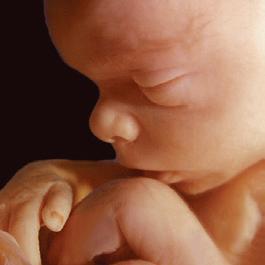

Day 1: Fertilization

The sperm joins with the egg to form one cell. This single cell contains the complex genetic makeup for every detail of a new human being. After fertilization, nothing new is added but oxygen, nutrition and time.1

1st Month: 1–4 Weeks

The first cell divides in two, and cell division continues as it travels down the fallopian tube to the uterus. Foundations of the brain, spinal cord, and nervous system are already established and by day 21 the heart begins to beat in a regular fashion.2 Muscles are forming, and arms, legs, eyes, and ears have begun to show.

2nd Month: 5–8 Weeks

By six weeks, brain waves can be detected.3 The jaw forms, including teeth and taste buds.4 The baby begins to swallow amniotic fluid, and sometimes hiccups.5 Fingers and toes are developing and at seven weeks the chest and abdomen are fully formed.6 Swimming in the amniotic fluid, she now looks like a miniature human infant.7,8

3rd Month: 9–12 Weeks

Unique fingerprints are evident and never change.9 The baby now sleeps, awakens, and exercises her muscles. The baby is very active. The gender can be visually determined and family resemblances may appear.10 At the end of the first trimester, all the organs and systems of her body are functioning.11

4th Month: 13–16 Weeks

By the end of the fourth month, the baby is 8–10 inches in length and weighs about one-half pound. Her ears are functioning and she hears her mother’s heartbeat, as well as external noises like music.12 Lifesaving surgery has been performed on babies at this age.

5th Month: 17–20 Weeks

If a sound is especially loud, the baby may jump in reaction to it. Thumb-sucking has been observed during the fifth month.13

6th Month: 21–24 Weeks

Oil and sweat glands are functioning. She grows rapidly in size and strength while her lungs become more developed.14

7th Month: 25–28 Weeks

The baby can now recognize her mother’s voice. She exercises by stretching and kicking. She uses the senses of hearing, touch and taste, and she can even look around with open eyes.15

8th Month: 29–32 Weeks

The baby swallows a gallon of amniotic fluid per day and often hiccups.16 The baby’s kicks are stronger and mom may be able to feel an elbow or heel against her abdomen.17

9th Month: 33–36 Weeks

Gaining one-half pound per week, the baby is getting ready for birth. The bones in her head are soft and flexible to more easily mold for the journey down the birth canal.18 Of the 45 generations of cell divisions before adulthood, 41 have already taken place. Only four more come before adolescence. Ninety percent of a person’s development happens in the womb.19